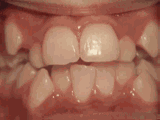

第三種---

前牙移位,因為有牙齒缺失,導(dǎo)致相鄰牙齒開始沒有秩序的亂移動,經(jīng)過矯正后是變成這樣的~